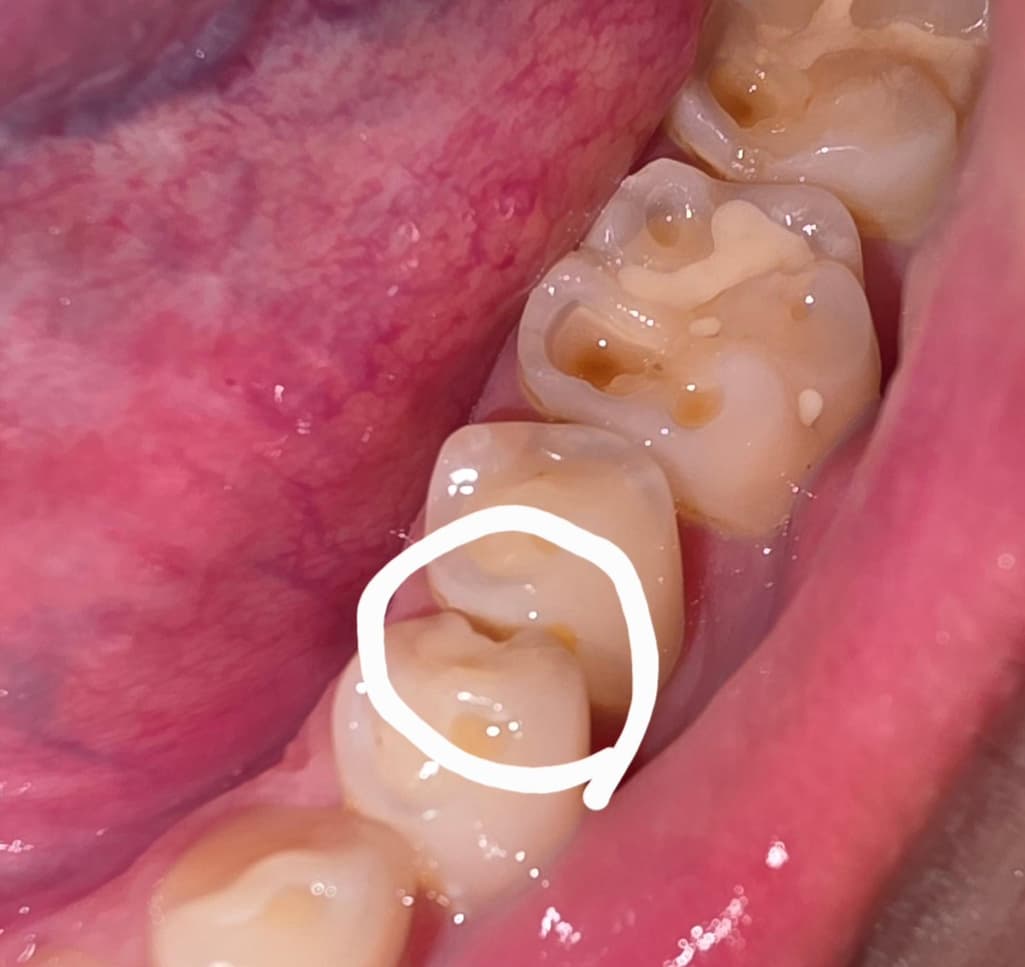

이가 홈이 생겻어요. 어떻게 치료를 하나요?

이가 어느샌가 보니 홈이 생겨져 잇드라구요

여긴 어떻게 치료하나요??....그냥 레진으로도 메꿀수잇나요??

시린느낌이나 통증은없어요

치아가 깨진거 같으니 치과에 가셔서 검진후 인레이치료 또는 크라운 치료를 받으셔야될수도 잇습니다.

치아의 인접면이 충치등으로 인해서 깨지거나 했다면 해당부위에 음식물이 자주 끼게 되어 충치가 더 커질수 있습니다. 치료를 해야 하는데 레진으로 인접면을 치료할경우 치아의 모양을 형성해주기 어려울수 있습니다.

이런경우에는 인레이나 크라운의 보철치료를 하게 됩니다.

이전에 떼운게 깨졌네요 치과가서 해당 부위 체크해보고 동일 재료로 떼울 수 있다면 떼우면 될 것 같습니다